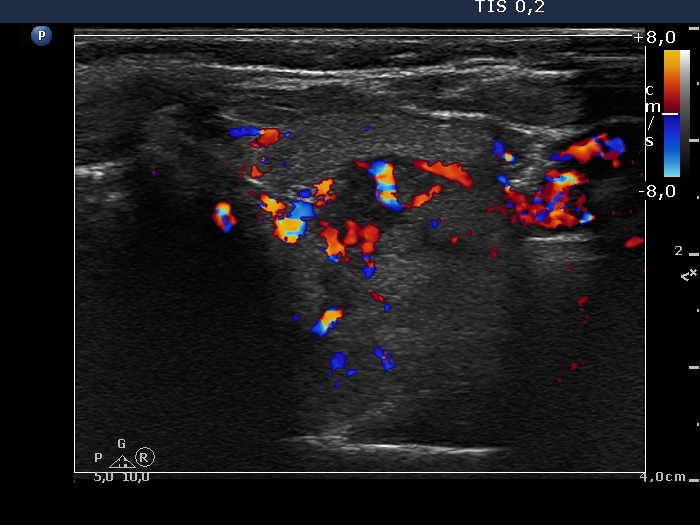

Intranodular hyperechogenic figures - case 1197 (ultrasonographic picture 6)

Upper part of the left lobe, transverse scan, color Doppler mode. The nodule displays both perinodular and intranodular vascularity.